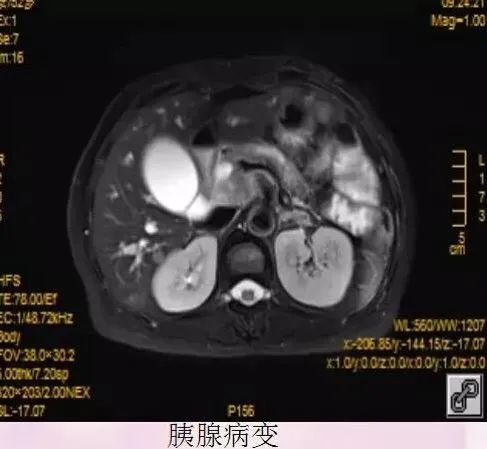

2.胰腺病变

肝癌、肝血管瘤及肝囊肿等肝脏占位性病变的诊断与鉴别诊断,腹内其他脏器肿块的诊断与鉴别诊断,尤其是腹膜后的病变。

❤ 磁共振腹部检查具有无创、无辐射等特点,绿色、安全,肝脏属于无痛性器官,大部分时候没有任何症状,多数病变是在体检中发现的。